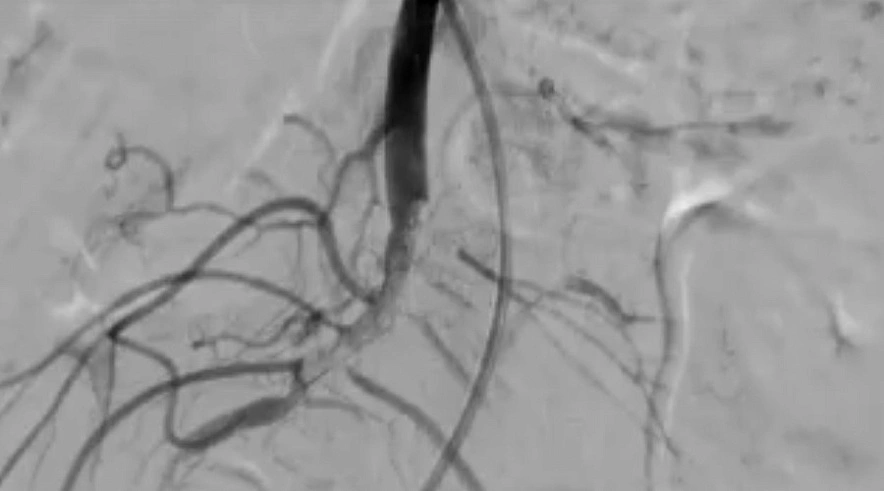

В Балаково медики провели уникальную операцию, использовав нестандартный способ лечения. Проявив сообразительность и мастерство, Балаковские врачи спасли пенсионерку с тяжелым диагнозом.

Как сообщает Балаковская городская клиническая больница (БГКБ), в приемное отделение поступила 78-летняя пенсионерка с тромбозом кишечника. Отличить на ранних этапах данное заболевание от других очень сложно, и окончательный диагноз врачи поставили уже непосредственно перед операцией. Медикам пришлось не только удалить омертвевшую часть кишечника, но и удалось необычным способом восстановить кровообращение в сосудах. По информации БГКБ, пенсионерку после операции внимательно наблюдали в течение недели, и сейчас уже выписали из больницы. А подробности уникальной операции балаковских медиков смотрите в репортаже БГКБ.